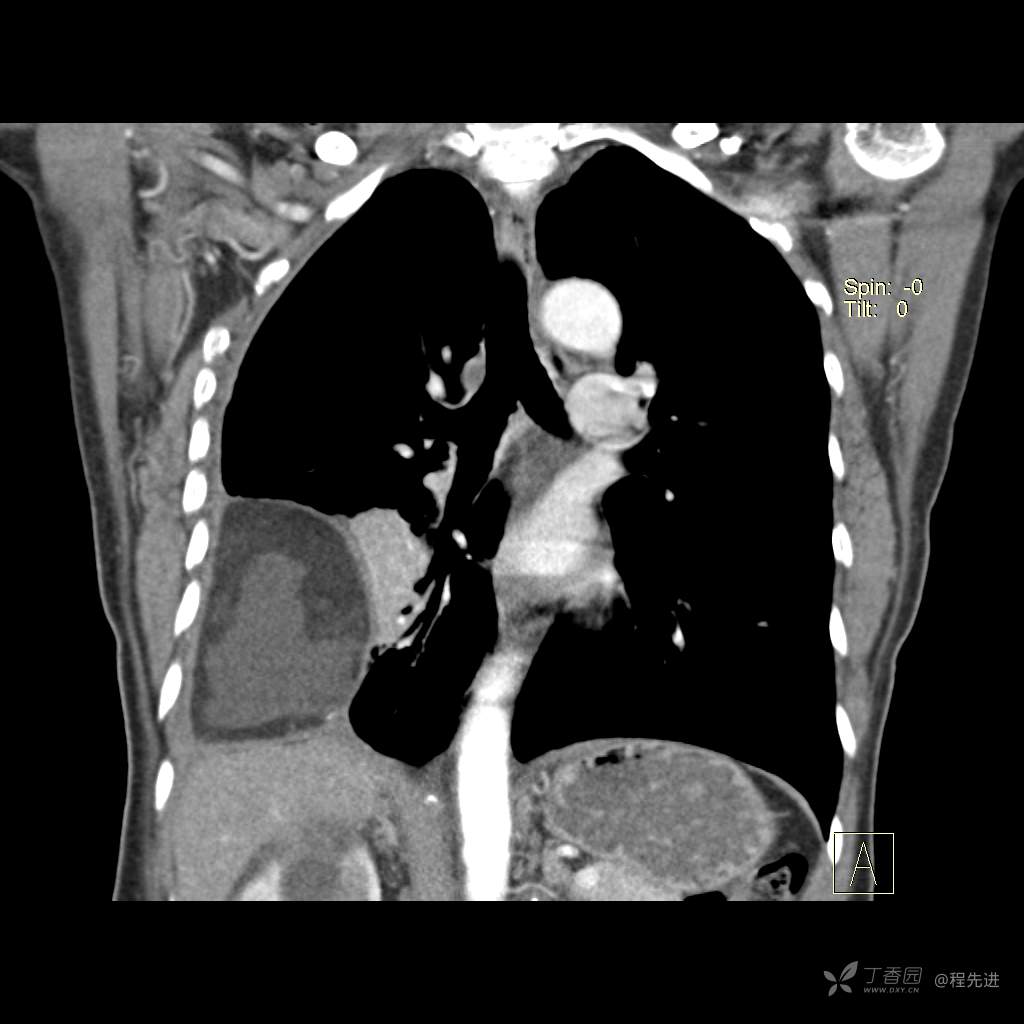

患者性别:女

患者年龄:51岁

简要病史:胸闷半年